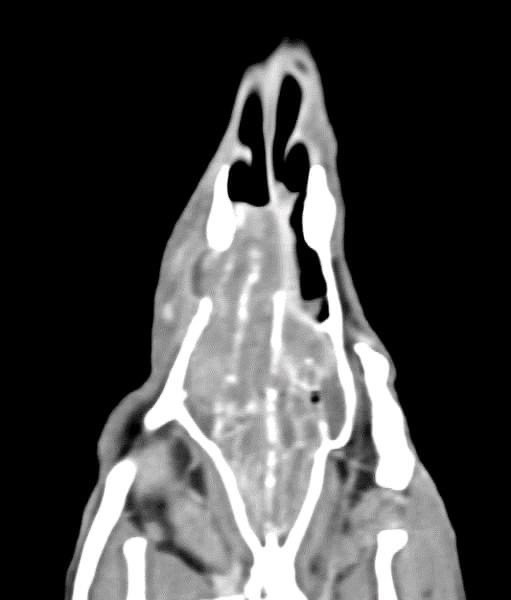

貓咪 鼻腔腫瘤腺癌 Adenocarcinoma

鼻腔腫瘤的診斷需要仰賴電腦斷層掃瞄定位病灶處,同時使用鼻腔內視鏡探查、採樣才能確診,同時有這兩項設備的醫院並不多,所以臨床事並不是那麼容易確診。貓咪幾個月前開始打噴嚏、流鼻、鼻塞越來越嚴重,他院住院治療改善不佳後轉診至築心檢查。

狗狗 鼻腔腫瘤 淋巴癌

鼻腔腫瘤的診斷需要仰賴電腦斷層掃瞄定位病灶處,同時使用鼻腔內視鏡探查、採樣才能確診,同時有這兩項設備的醫院並不多,所以臨床事並不是那麼容易確診。狗狗如果有打噴嚏、鼻分泌物 鼻塞,對藥物治療反應不好, 就還是要做進一步檢查才會比較安心唷!

鼻上皮細胞癌

鼻腔症狀是門診中狗貓最常見的主訴之一,但在診斷上卻不那麼容易,在缺乏如電腦斷層、內視鏡、牙科X光等特定設備的情況下,門診醫師多只能嘗試性的給藥觀察,對於慢性、頑固、難治的鼻腔問題往往便束手無策了。

柴犬皮皮因長期有鼻塞、流鼻血、流鼻水的症狀來築心就診,在這之前已經換過兩間醫院,但治療效果都不太好。在一系列的評估後,我們為皮皮安排了電腦斷層以及鼻腔內視鏡的檢查,檢查後發現在皮皮的鼻腔內有疑似腫瘤的團塊,並且向後侵入鼻竇,甚至已經接近大腦。我們運用內視鏡設備採樣取得了團塊的切片,並得到鼻上皮細胞癌的診斷。